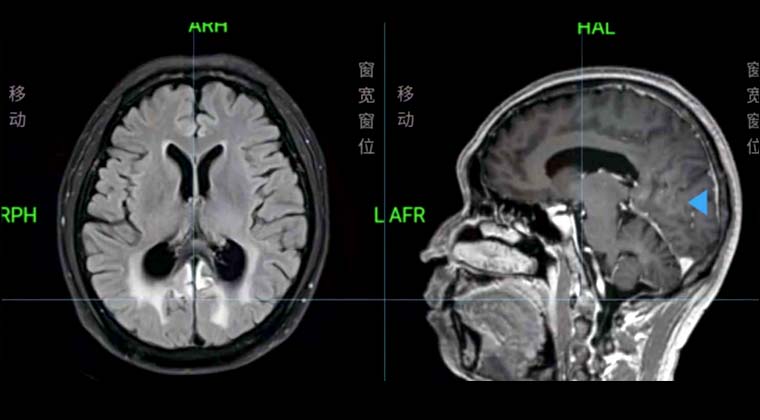

Пациентка женщина, 59 лет

Рак мочевого пузыря

29.02021 проведено PET/CT обследование: выявлены множественные очаги на передней, задней стенках и дне мочевого пузыря, предполагается рецидив опухоли.

Проведена одновременная химиолучевая терапия (монотерапия цисплатином 20 мг/м² еженедельно) с облучением таза по VMAT 45 Гр, с локальным бустом мочевого пузыря 20 Гр, с применением IGRT.

Через месяц после лучевой терапии контрольное МРТ таза не выявило остаточных опухолевых очагов или признаков рецидива в мочевом пузыре.

До лечения:

После лечения: